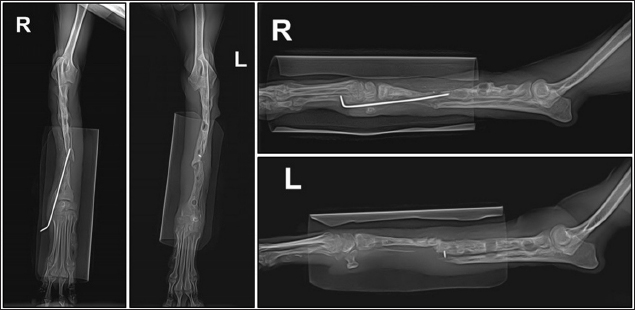

A 3-year and 6-month-old Toy Poodle presented with a history of failed treatment for bilateral radius and ulnar fractures over the course of 1 year. The initial treatment involved plate fixation and linear external fixation; however, repeated implant failure resulted in a non-union fracture (Fig. 1). At the time of presentation, radiographs revealed that most plates, screws, and pins had been removed from both limbs. The prolonged non-union resulted in continued bone resorption at the fracture site without any signs of healing. Loosening was evident around the bone holes where the fixation devices had been applied, and some pins were still visible on the radiographs, indicating they had not been removed. The dog mainly used its hind limbs and exhibited a plantigrade gait when moving the forelimb. Overall systemic conditions were satisfactory. No specific abnormalities were found in the skin surrounding the fracture site or pin insertions, and blood tests showed normal results, except for a slight increase in alkaline phosphatase. The diagnosis was confirmed as non-union fractures of the radius and ulna in both forelimbs.

Fig. 1. Bilateral radiographs of the radius and ulna, showing osteolytic bone holes at previous screw sites and nonunion at the fracture sites.